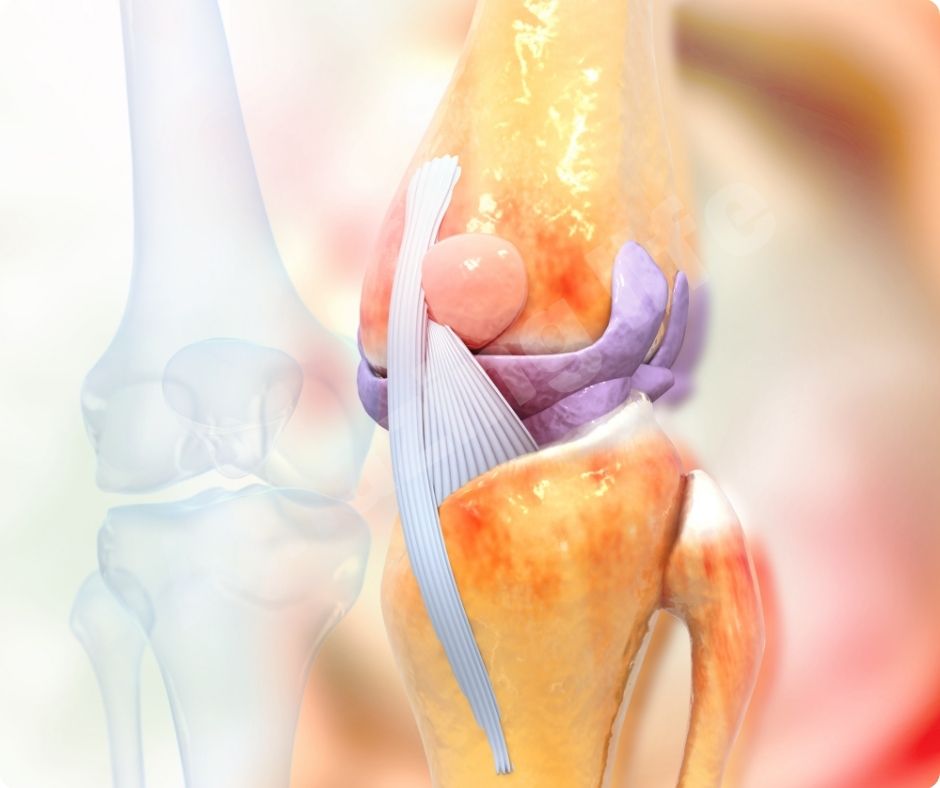

관절 통증 완화

많은 연구에서 글루코사민의 효능이 관절 통증을 완화하는 데 효과적이라는 결과가 나왔습니다. 최근 연구에 따르면, 글루코사민과 콘드로이틴 보충제를 꾸준히 섭취하면 심혈관 질환 사망률이 65%까지 감소할 수 있습니다.

연골 보호 및 재생

글루코사민은 연골 조직의 구성 요소로서 연골의 손상을 막고 재생을 촉진합니다. 이는 특히 고령자나 관절에 많은 부담이 가는 운동을 하는 사람들에게 중요합니다. 글루코사민의 연골 보호 효과는 관절염의 진행을 늦추고 삶의 질을 향상시키는 데 큰 도움을 줍니다.

염증 감소

글루코사민의 효능은 염증을 감소시키는 데도 효과적입니다. 관절염은 염증으로 인해 발생하는 경우가 많으므로, 글루코사민을 통해 염증을 줄이면 관절염 증상을 완화할 수 있습니다. 이는 자연적인 방법으로 관절 건강을 유지하는 데 유용합니다.